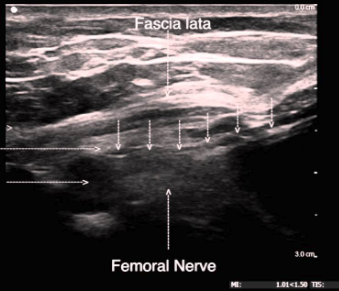

Arrow is Pointing at What Structure?

What is this view?

Identify the Block and Following Structures

Complications?

What is a “3 in 1” Block

What Nerves Are Blocked?